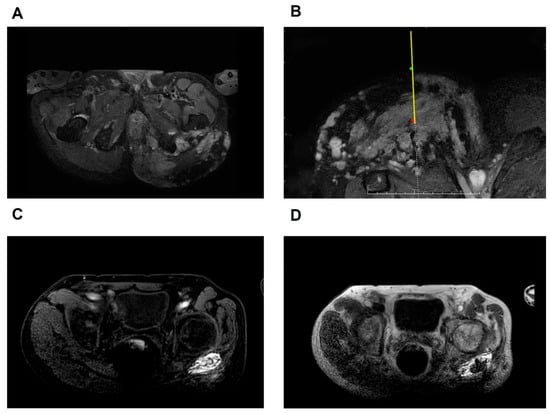

Figure 3. Diagram of the surgical process. The green spots indicate the entry point, the red dots represent the puncture target, the yellow lines illustrate the needle, and the dotted lines depict its trajectory toward the target. (A) Pre-treatment axial fast mDIXON T2-weighted image demonstrating the venous malformation located in the left hip joint; (B) fast mDIXON T2-weighted image showing the position of the needle and its tip reaching the target area; (C) FFE T1-weighted image following the injection of contrast agent; (D) fast mDIXON T2-weighted image post-injection of the sclerosing agent. FFE, fast field echo; mDIXON, modified DIXON.